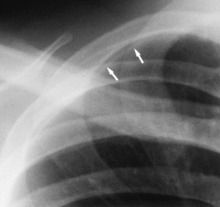

A rib companion shadow (indicated by two arrows)

- Rib companion shadows parallel the ribs and measure 1–5 mm in diameter project adjacent to the inferior and inferolateral margins of the first and second ribs and the axillary portions of the lower ribs. These companion shadows of the first and second ribs occur in 35% and 31% of the population, respectively. Rib companion shadows represent the fat and muscles in the intercostal space. The shadows that accompany the ribs may mimic pleural and lung disease.[2]